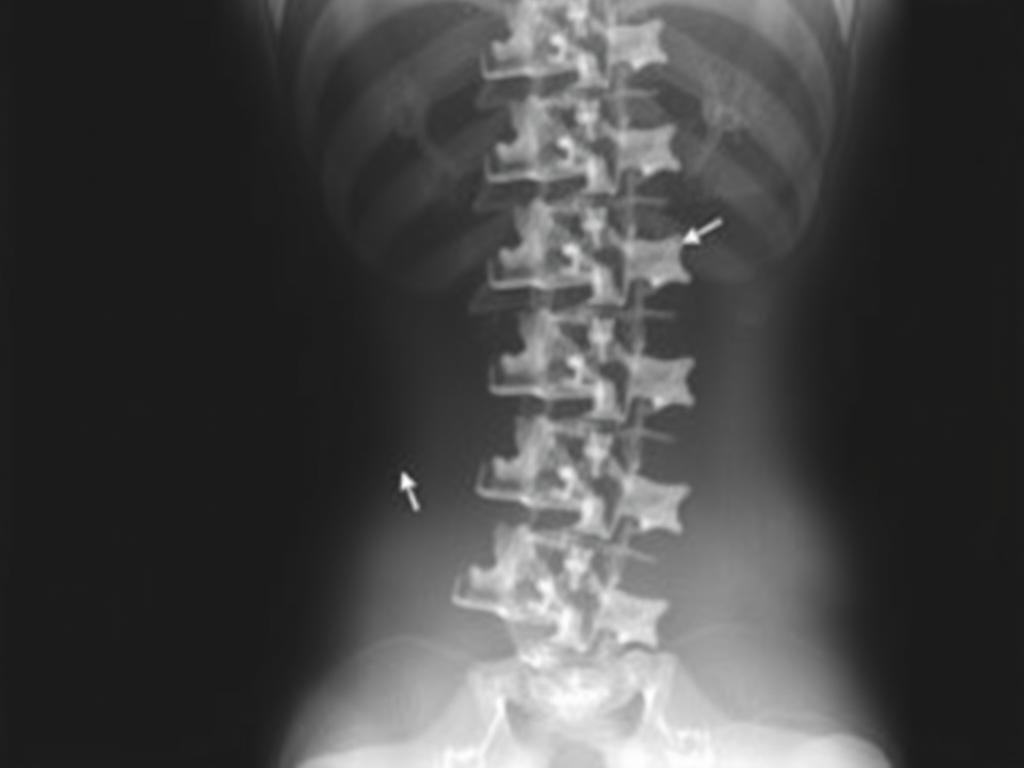

Röntgenbild: Deutlich erkennbares Wirbelgleiten in der Lendenwirbelsäule

Bildgebende Verfahren

Röntgenuntersuchung

Standardaufnahmen der Wirbelsäule im Stehen zeigen die Knochenstrukturen und können ein Wirbelgleiten sichtbar machen. Manchmal werden zusätzlich Funktionsaufnahmen in Vor- und Rückbeuge angefertigt, um die Stabilität der Wirbelsäule zu beurteilen.